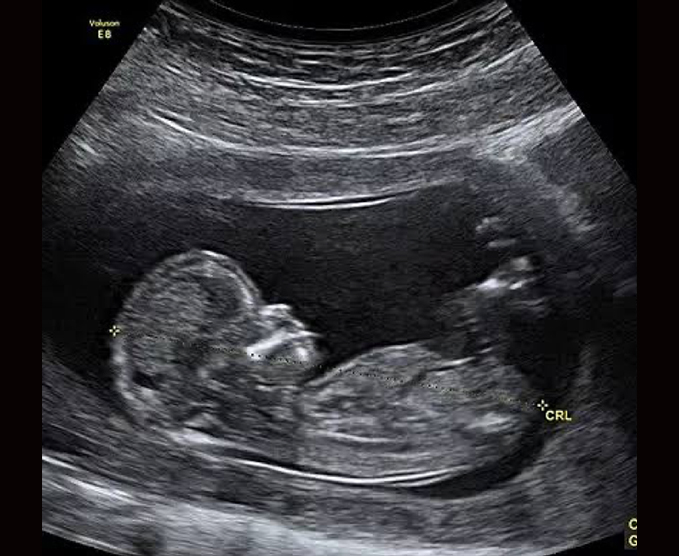

El ultrasonido obstétrico utiliza ondas sonoras para producir imágenes de un bebé (embrión o feto) que está dentro de una mujer embarazada, como así también del útero y los ovarios de la madre. No utiliza radiación ionizante, no tiene efectos nocivos conocidos, y es el método preferido para la vigilancia de las mujeres embarazadas y sus bebés que aún no han nacido.

- Ultrasonido transabdominal

- Ultrasonido transvaginal